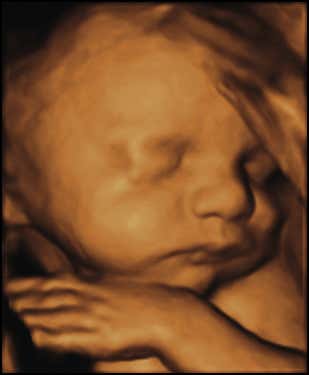

3D ultrasound image of a foetus at 28 weeks

Conventional ultrasound, usually offered to mothers at 12 and 20 weeks, produces 2D images of the developing foetus. In 1989, however, a company called Kretztechnic from Austria (founded by Carl Kretz) produced the first commercial 3D scanner. It produced still surface images of the fetus in three dimensions, like the one you can see here.

To produce 3D scans, rather than the sound waves being sent straight down and reflected back as they are in 2D scans, they are transmitted at different angles. The returning echoes are interpreted by a computer program, which produces a reconstructed 3D image.

Since the early 1970s, ultrasound scans have become symbols for the anti-abortion movement, especially in the US. Recently, elaborate 3D and 4D scans – the fourth dimension being time – have been used in heated public campaigns to lower the upper age limit for abortion.

The routine use of ultrasound has also changed the way parents relate to their future children. The first photographs in baby albums now usually predate birth.